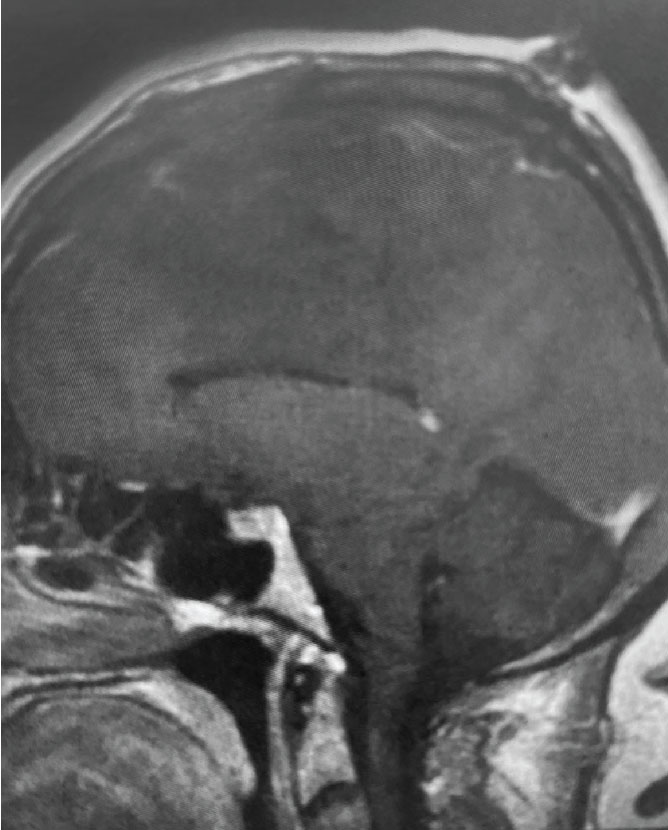

Fig 1. B) Pre-operative, sagittal post-contrast MRI.

This is a 55 year old right-handed woman who was having progressive balance problems. MRI with and without contrast demonstrated a 7 cm partly cystic meningioma involving the left frontal convexity and falx, and encasing the superior sagittal sinus. There was also tumor involvement of part of the convexity skull.

Treatment: Given the size and location of this tumor, the best treatment was surgical removal. Surgery was performed by Dr. Michael Brisman. A craniotomy exposed the tumor along the convexity as well as the superior sagittal sinus. The tumor was removed, as was the involved convexity dura and the affected segment of the sagittal sinus. Removed dura and skull were replaced with duraplasty (with artificial dura) and a titanium mesh cranioplasty.